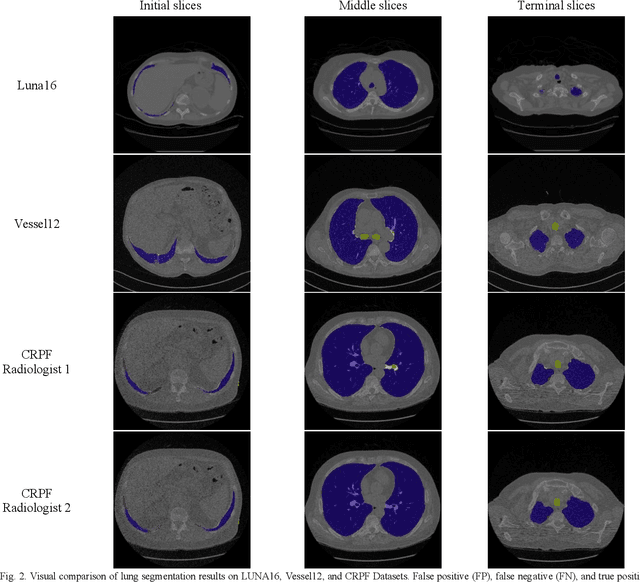

Abstract:Segmentation of lung tissue in computed tomography (CT) images is a precursor to most pulmonary image analysis applications. Semantic segmentation methods using deep learning have exhibited top-tier performance in recent years. This paper presents a fully automatic method for identifying the lungs in three-dimensional (3D) pulmonary CT images, which we call it Lung-Net. We conjectured that a significant deeper network with inceptionV3 units can achieve a better feature representation of lung CT images without increasing the model complexity in terms of the number of trainable parameters. The method has three main advantages. First, a U-Net architecture with InceptionV3 blocks is developed to resolve the problem of performance degradation and parameter overload. Then, using information from consecutive slices, a new data structure is created to increase generalization potential, allowing more discriminating features to be extracted by making data representation as efficient as possible. Finally, the robustness of the proposed segmentation framework was quantitatively assessed using one public database to train and test the model (LUNA16) and two public databases (ISBI VESSEL12 challenge and CRPF dataset) only for testing the model; each database consists of 700, 23, and 40 CT images, respectively, that were acquired with a different scanner and protocol. Based on the experimental results, the proposed method achieved competitive results over the existing techniques with Dice coefficient of 99.7, 99.1, and 98.8 for LUNA16, VESSEL12, and CRPF datasets, respectively. For segmenting lung tissue in CT images, the proposed model is efficient in terms of time and parameters and outperforms other state-of-the-art methods. Additionally, this model is publicly accessible via a graphical user interface.